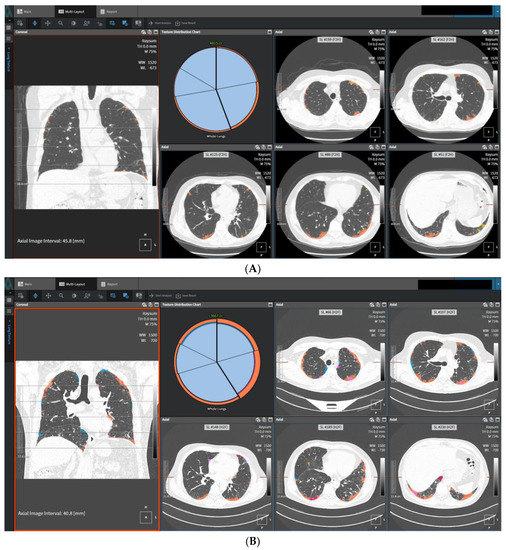

- Maldonado, F.; Moua, T.; Rajagopalan, S.; Karwoski, R.A.; Raghunath, S.; Decker, P.A.; Hartman, T.E.; Bartholmai, B.; Robb, R.A.; Ryu, J. Automated quantification of radiological patterns predicts survival in idiopathic pulmonary fibrosis. Eur. Respir. J. 2014, 43, 204–212. [Google Scholar] [CrossRef]

- Romei, C.; Tavanti, L.M.; Taliani, A.; De Liperi, A.; Karwoski, R.; Celi, A.; Palla, A.; Bartholmai, B.J.; Falaschi, F. Automated Computed Tomography analysis in the assessment of Idiopathic Pulmonary Fibrosis severity and progression. Eur. J. Radiol. 2020, 124, 108852. [Google Scholar] [CrossRef]

- Jacob, J.; Bartholmai, B.J.; Rajagopalan, S.; Kokosi, M.; Egashira, R.; Brun, A.L.; Nair, A.; Walsh, S.L.F.; Karwoski, R. Serial automated quantitative CT analysis in idiopathic pulmonary fibrosis: Functional correlations and comparison with changes in visual CT scores. Eur. Radiol. 2018, 28, 1318–1327. [Google Scholar] [CrossRef] [PubMed]

- Joseph, J.; Brian, J.B.; Srinivasan, R.; Maria, K.; Arjun, N.; Ronald, K.; Sushravya, M.R.; Simon, L.W.; Athol, U.W.; David, M.H. Automated Quantitative Computed Tomography Versus Visual Computed Tomography Scoring in Idiopathic Pulmonary Fibrosis: Validation Against Pulmonary Function. J. Thorac. Imaging 2016, 31, 304–311. [Google Scholar]